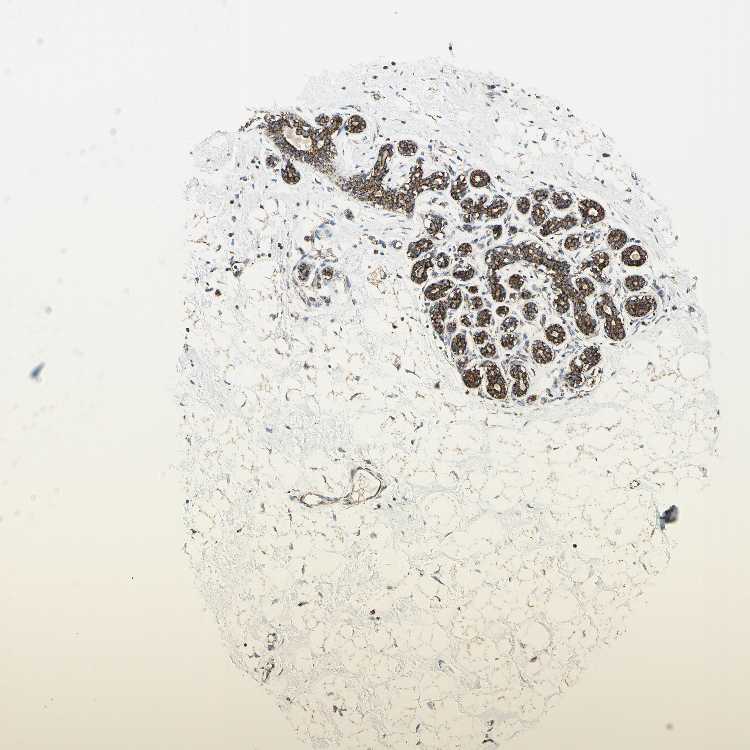

BREAST - Antibody stainingi

Antibody staining in the annotated cell types in the current human tissue is reported as not detected, low, medium, or high, based on conventional immunohistochemistry profiling in selected tissues. This score is based on the combination of the staining intensity and fraction of stained cells.

Each image is clickable and will lead to virtual microscopy that enables deeper exploration of all samples and also displays staining intensity scores, fraction scores and subcellular localization as well as patient and tissue information for each sample.

Antibody HPA049850Antibody HPA053524Antibody CAB009187

Glandular cells MediumMediumHigh